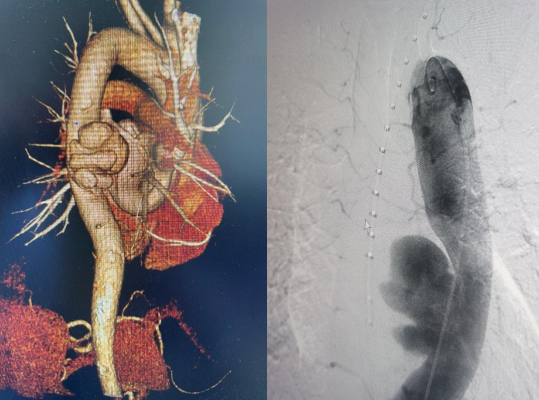

近日,MILAN.COM胸心外科收治了一名胸主动脉瘤患者。患者58岁,男性,6月前出现腰背部疼痛不适,症状持续不缓解,多次就诊于当地医院。完善相关检查未见明显异常,给与止痛药物口服对症治疗,症状较前稍缓解。期间,上述症状间断发生。2周前,患者腰背部疼痛转移到胸背部疼痛,继而向前胸部扩展,疼痛无法耐受,就诊于市中心医院。入院后,胸主动脉CTA检查提示“胸主动脉瘤”,大小4.5x6.4x6.8cm,破口上下径2.8cm,胸心外科以“胸主动脉瘤”收治进一步治疗。

如胸主动脉瘤破口继续撕裂,大血管随时破裂,几乎没有抢救机会,几分钟就会导致患者死亡。为挽救患者生命,在胸心外科副主任姜永红的带领下,副主任医师杨勇、护士长孙金艳及时上报医务科,积极MDT讨论。主管领导焦建雄组织胸心外科、麻醉手术室、心内科、重症医学科、介入科、神经内科、超声诊断科、输血科、药剂科等相关科室会诊,讨论病例,分析病情,制定可行性治疗方案,最大限度保障患者安全。经过讨论,结合患者年龄、身体状况和基础疾病情况,决定积极处理胸主动脉瘤,运用目前先进有效、最小损伤的介入治疗方案---胸主动脉覆膜支架腔内隔绝术。各科室明确各自职责分工,做好应急预案准备。

经过胸心外科、介入科、麻醉手术室、超声科多学科协作,于11月4日下午4点在急诊局麻下行胸主动脉覆膜支架夹腔内隔绝术,术中精准释放覆膜支架,复查血管造影显示,封闭主动脉破裂口,无内漏,支架位置良好,术区相关动脉血管显影良好,“不定时炸弹”成功拆除。术后给予患者抗板、止痛、控制血压等相应治疗,患者目前恢复良好,已顺利出院。该手术的成功,充分体现了我院多学科积极协作的团队精神。